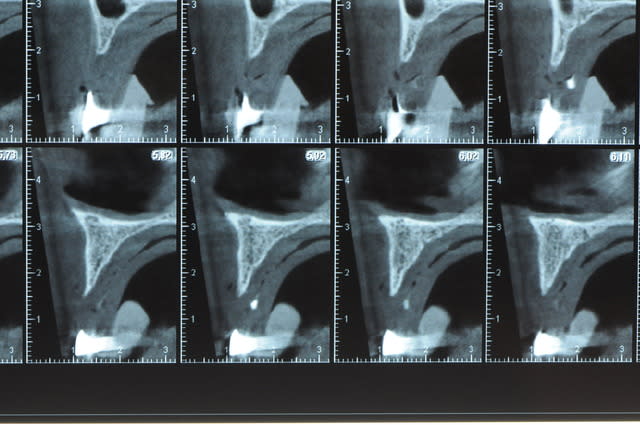

j'ai besoin de 4 implants au maxillaire pour faire tenir son complet.

dans la zone postérieur, pas de problème, mais devant, c'est une autre histoire.

Non sans décorner, superbe cas de début pour expansion, bone splitting et tout et tout.

la corticale a l'air tiptop, par contre en cas d'expansion il faut eventuellemnt augmenter le nombre d'implant à 6 pour compenser eventuellement le manque d'epaisseur 'avis personnel)

Je suis sceptique sur la gestion de ce cas par bone splitting puisqu'il met parait très difficile d'obtenir un volume osseux peri-implantaire crestal suffisant et satisfaisant.

+1 Olive, ce serait à mon avis plus prédictible avec des greffes. Je doute qu'on puisse obtenir suffisamment d'os en vestibulaire et en palatin des implants en splittant une crête aussi fine.

J’ai pratiquement les mêmes résultats que dans l’implanto classique, si j’ai 3 mm d’os en épaisseur.

Si je dispose de 2mm j’ai encore 85% de succès

À environ 1,5 mm je descends à 50% (c’est bas mais ça veut dire qu’un cas sur deux bénéficie d’implants alors que normalement ......)

De ce que j’ai vu du cas de D57 c’est me semble t il un magnifique cas d’expansion, ce qui ne veut pas dire rien d’autre

Une petite étude de ton cas D57

Sous réserves bien sur de voir l’animal en vrai

Les zones exploitables radiologiquement parlant:

Coupes implant

2,3 40100

4,96 35130 avec sinus lift mais difficile

5,25 35150

6,02 35130

6,78 35115 après réduction de hauteur de crête

7,26 35115 après réduction de hauteur de crête

8,51 35150

10,43 40115 ou 50115

11,10 40115

Ce qui nous fait 9 implants possible évidement avec un comblement de sinus on augmenterait encore les zones implantable mais ce n’est pas le but recherché, avec 8 (4+4) il doit être possible de faire une belle barre support de complet